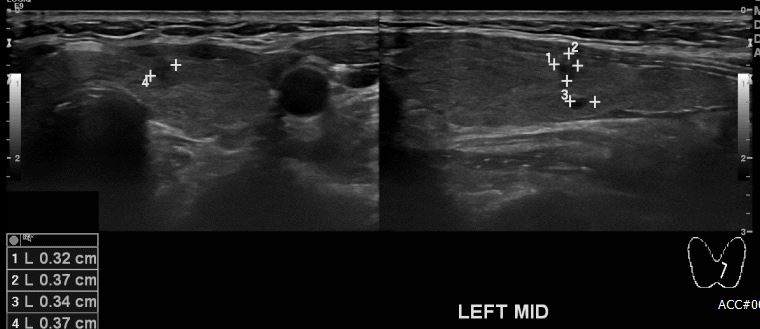

상기환자 갑상선의 멍울로 타원 경과관찰 하시던 50대 여성분으로 본원 갑상선 초음파상 좌측 갑상선에 의심스러운 멍울 세침검사 시행하여 좌측 갑상선 유두암 진단 되었습니다.